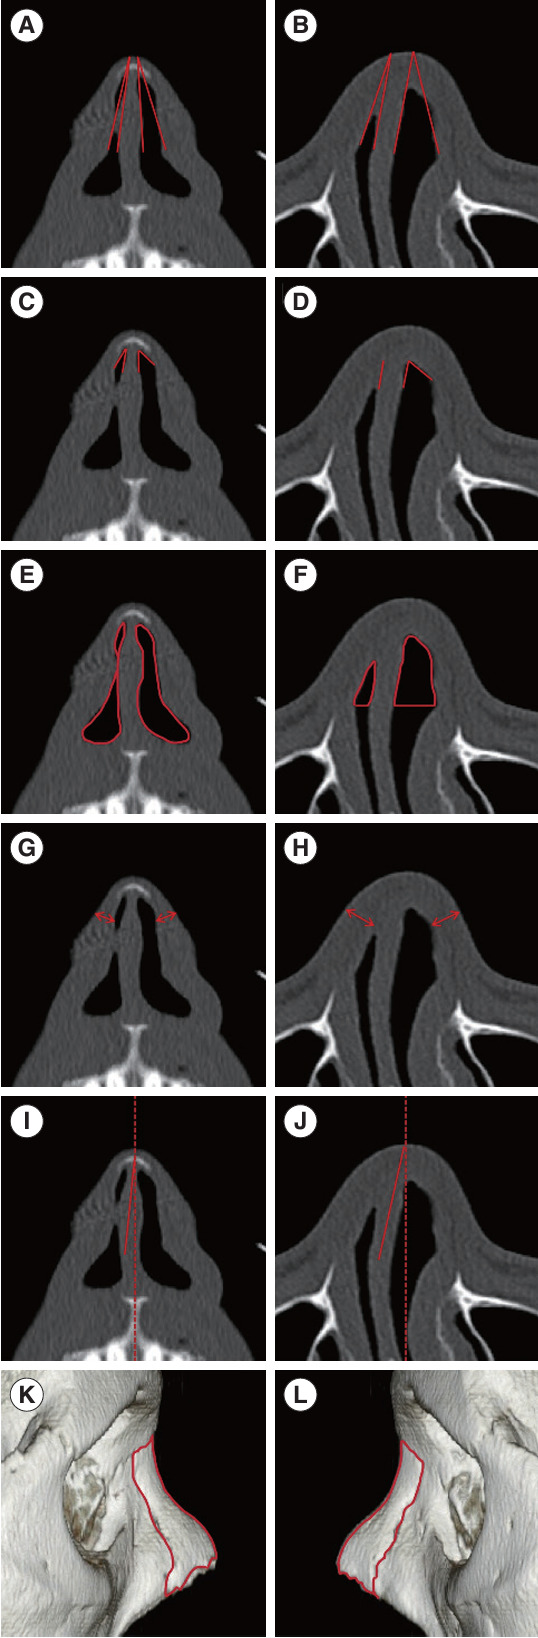

Methods: We analyzed 186 INVs in 93 patients who underwent nasal valve surgery. The data comprised facial computed tomography (CT) images, acoustic rhinometry, the modified Cottle test, and symptom scores. Patients were categorized based on their symptoms and the.

Results: of the modified Cottle test. We measured the INV angle, area, volume, lateral wall thickness, septal angle, and nasal bone area using CT.

Results: The compromised INV group, characterized by nasal obstruction with a positive modified Cottle test, exhibited smaller INV areas in both coronal and axial views, reduced INV volume in the axial view, and a thinner lateral wall in the coronal view (all P<0.05). Acoustic rhinometry indicated a smaller minimal cross-sectional area and volume in the compromised INV group (both P<0.001). Regression analysis demonstrated significant associations between a compromised INV and reduced INV area on the axial view, as well as the minimal cross-sectional area measured by acoustic rhinometry.

Conclusion: Relying solely on the INV angle in CT scans has limitations in assessing compromised INV. Alternatively, the INV area on axial CT scans and the minimal cross-sectional area measured by acoustic rhinometry may serve as objective parameters for evaluating INV compromise.